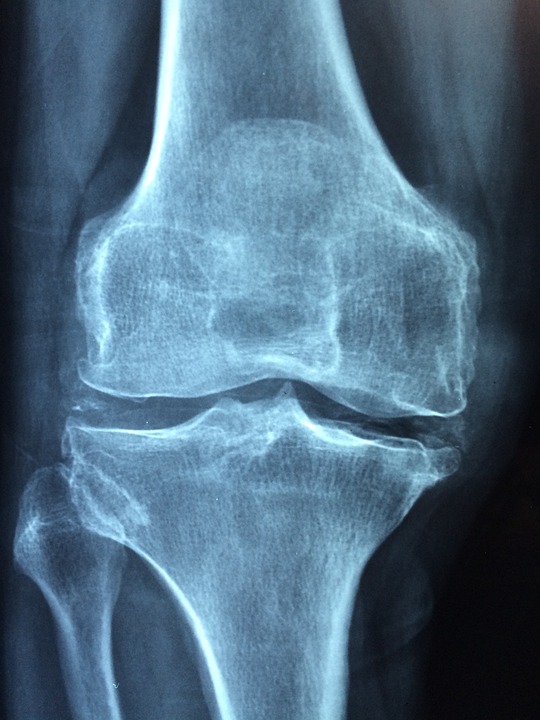

골다공증은 뼈의 밀도가 감소하고

뼈 조직의 변화로 인해 뼈가 약해지는 질환입니다.

이로 인해 뼈가 쉽게 파괴되고, 부러지거나 골절하기 쉬워집니다.

골다공증은 뼈의 밀도가 감소하여 뼈가 취약해지는 질환입니다.

이러한 취약한 뼈는 심각한 상황에서는 심한 골절을 유발할 수 있습니다